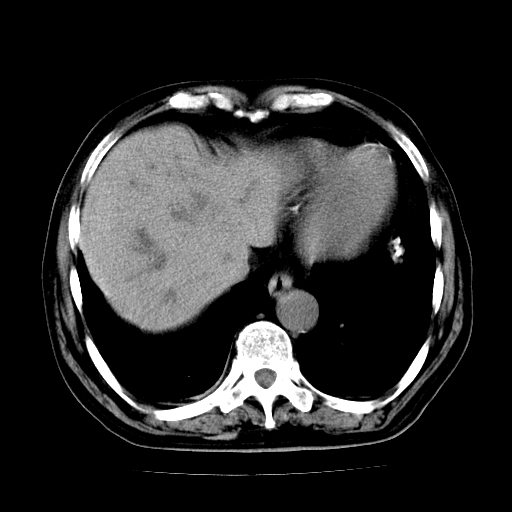

标题: CT25226:男,71岁,皮肤黄染四天。 [打印本页]

男,71岁,皮肤黄染四天。

肝内外胆管及胆总管上段扩张,考虑为梗阻所致,建议mrcp检查。

考虑胆总管癌并肝内外胆管扩张。

支持考虑胆总管癌并肝内外胆管扩张。 局部应薄扫。心包钙化。

胰腺上端胆总管内见软组织影,强化不明显,结合临床,还是考虑低位梗阻性黄疸,胆总管癌可能性大